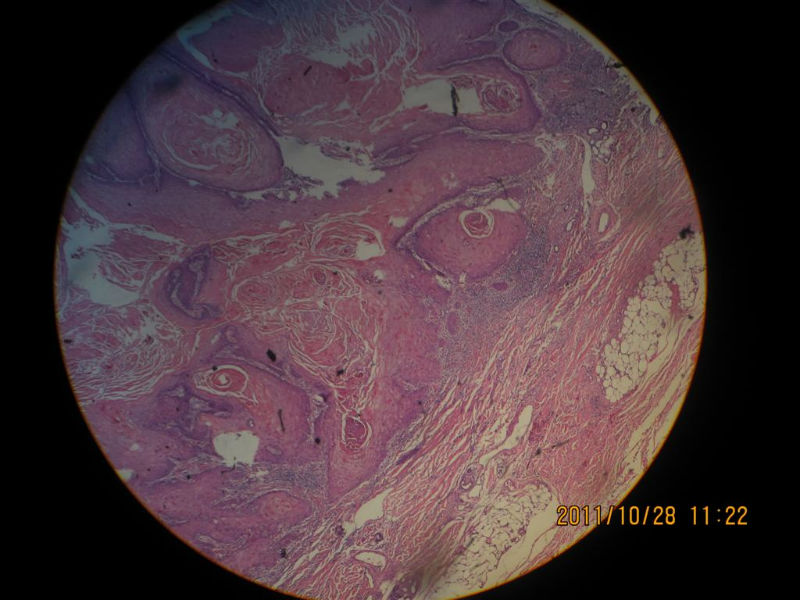

女性,71岁,右前臂肿物。角化棘皮瘤还是高分化鳞癌?

图1

图2

图3

图4

图5

图6

图7

图8